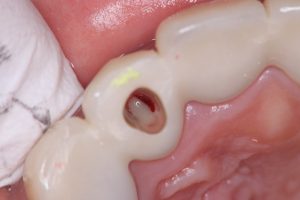

代診医から代わり、私が探り意図的穿通💪No.2

リーマ100号に相当、径0.95ミリ位

白のファイバーだから見え難い

多量に排膿と出血